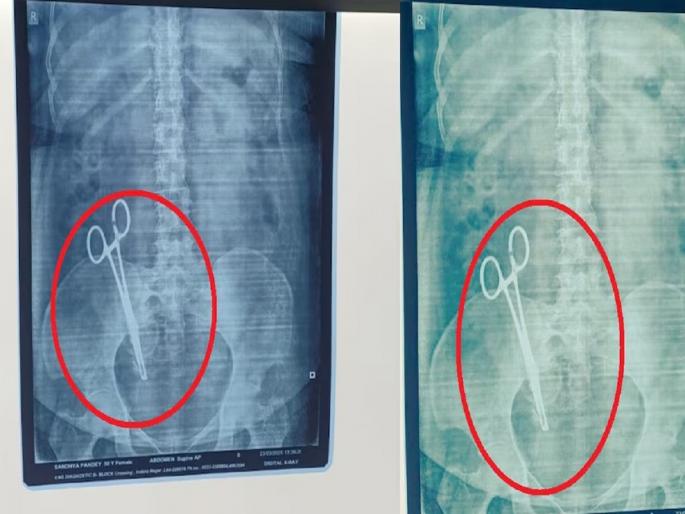

UP News : उत्तर प्रदेशातून एक धक्कादायक प्रकरण समोर आले आहे. राजधानी लखनऊमध्ये 17 वर्षांपूर्वी सिझेरियन ऑपरेशनदरम्यान महिलेच्या पोटात कात्री विसरल्याची घटना घडली होती. आता इतक्या वर्षांनंतर महिलेचा एक्स-रे करण्यात आला, तेव्हा ही घटना उघडकीस आली. याप्रकरणी महिलेच्या पतीने गाझीपूर पोलीस ठाण्यात तक्रार दाखल केली आहे.

अलीकडेच महिलेच्या पोटाचा एक्स-काढण्यात आला, यादरम्यान पोटात चक्क कात्री आढळली. यानंतर तिला किंग जॉर्ज मेडिकल युनिव्हर्सिटी (KGMU) मध्ये दाखल करण्यात आले. 26 मार्च रोजी एका जटिल शस्त्रक्रियेनंतर डॉक्टरांनी कात्री काढली. यानंतर अरविंद पांडे यांनी नर्सिंग होमच्या डॉक्टराविरुद्ध गाझीपूर पोलिसांत तक्रार दाखल केली आहे. या निष्काळजीपणामुळे पत्नीला 17 वर्षे शारीरिक आणि मानसिक त्रास सहन करावा लागल्याचा आरोप त्यांनी केला.